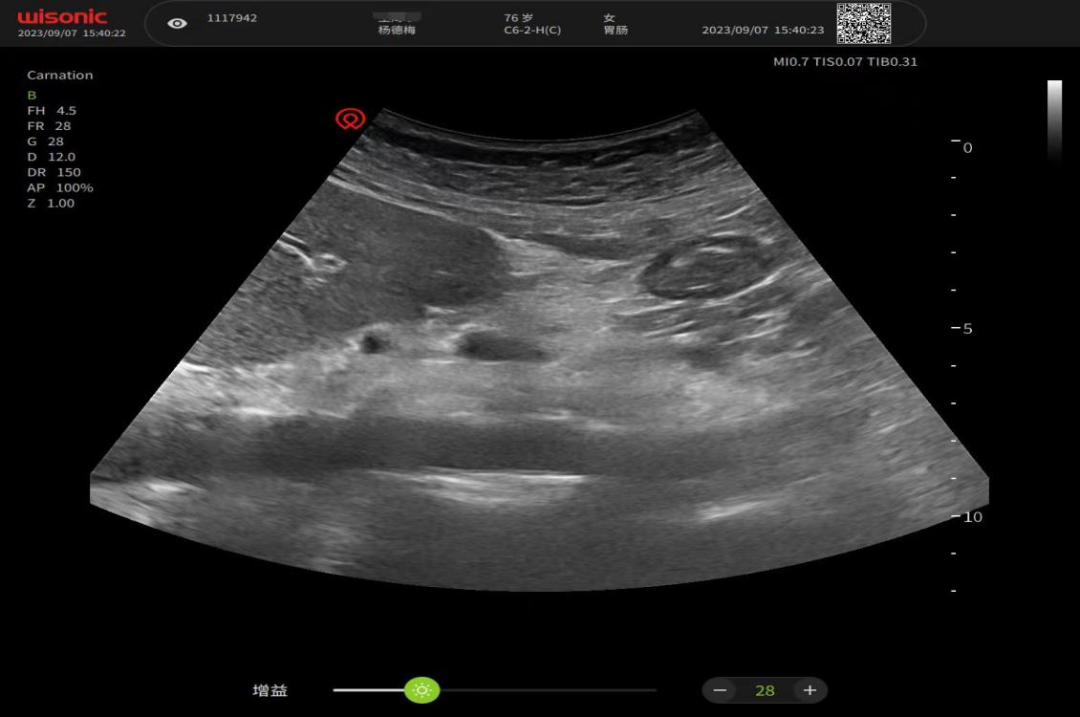

胃肠道监测

重症护理超声导向的胃肠功能评估有助于指导重症患者肠内营养的安全,实施胃肠功能评估,包括胃残余量、胃动力、胃排空情况和肠蠕动度等多项内容,从而优化营养治疗方案,避免反流误吸和营养不足等情况。